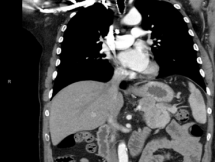

His oral glucose tolerance confirmed him to be diabetic. His CT scan showed a large pancreatic mass with involvement of lymph nodes and local infiltration (Figure 2,3).

Figure 2 Pancreatic mass with lymph node involvement.

Figure 3 Pancreatic mass with local tissue invasion.